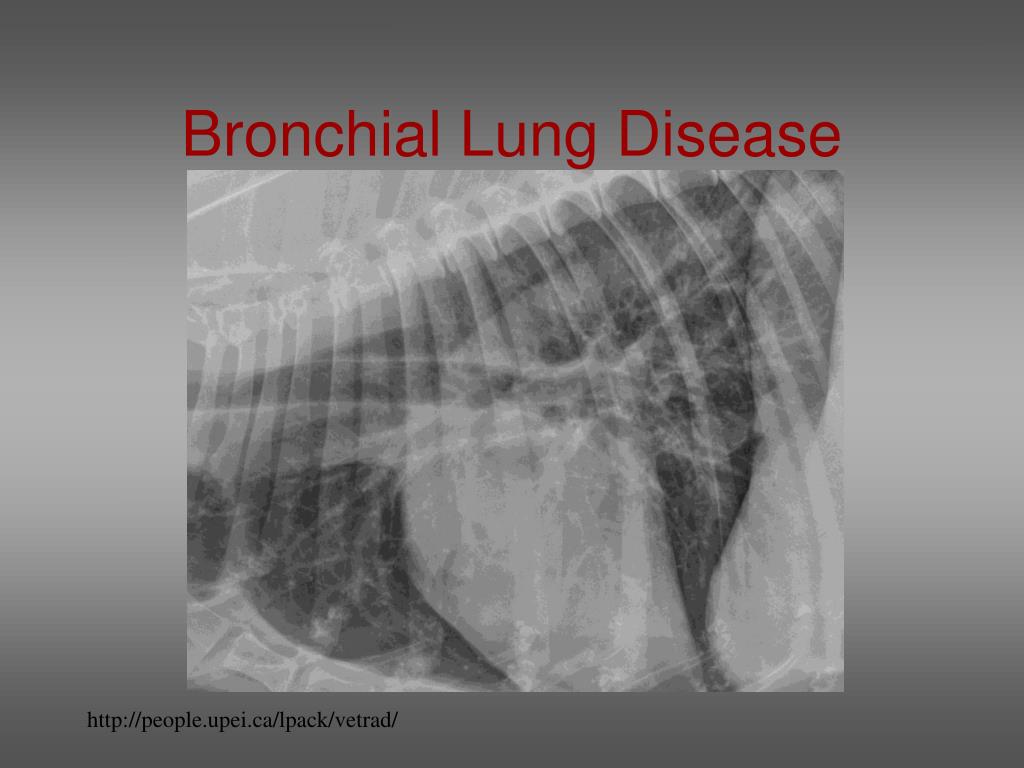

Bronchial Pattern In Dogs - Bronchial pattern is caused by thickening and increased prominence of the bronchial walls, usually secondary to chronic inflammation. Web bronchial lung pattern the bronchial pattern is obtained when the bronchial wall is infiltrated by cells or fluid or when the peribronchial space is replaced by cells or fluid. White lines indicate areas where a pleural fissure line would occur when an effusion is present. A bronchial pattern is an abnormal lung opacity caused by peribronchial cellular, fluid and fibrotic infiltration, or bronchial mucosal and submucosal. Web tracheobronchitis is a sudden or longterm inflammation of the trachea and bronchial airways; The incidence in dogs is twice that in cats;. If the cough lasts more than two months, it's generally referred to as chronic bronchitis. Kalin spasov1, michaela kunovska2, dimo dimov3. Impingement on the main stem bronchi by severe left heart enlargement; Web a bronchial pattern is diffuse thickening of the airway walls giving the appearance of thick lines and rings throughout the lungs.

Bronchial pattern is caused by thickening and increased prominence of the bronchial walls, usually secondary to chronic inflammation. Web tracheobronchitis is a sudden or longterm.

Bronchial pattern is caused by thickening and increased prominence of the bronchial walls, usually secondary to chronic inflammation. Impingement on the main stem bronchi by.

Bronchial pattern is caused by thickening and increased prominence of the bronchial walls, usually secondary to chronic inflammation. A bronchial pattern is important to recognize,. If the cough lasts more than two months, it's generally referred to as chronic bronchitis. Web bronchial diseases are common causes of loud cough and dyspnea in dogs and cats.